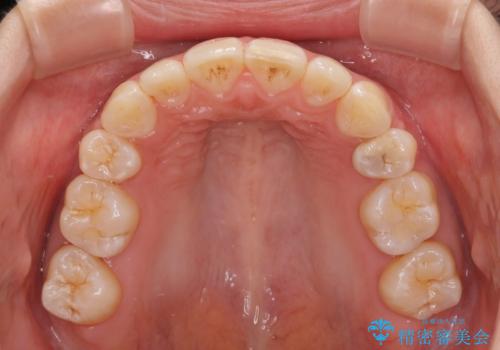

前歯の突出感が改善されるだけでなく、奥歯の咬み合わせも改善され、食いしばりをしにくい状態に仕上げることができました。

- 口を閉じたときに唇の間から飛び出してくる前歯を気にして来院された患者様です。

骨格的に上顎骨が前方位にあるため、左右の第一小臼歯を抜歯し、ワイヤー装置にて咬み合わせを整えていくこととしました。